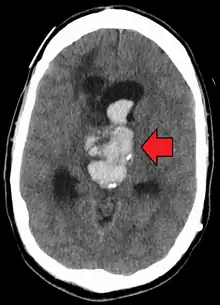

Axial CT scan of a spontaneous intracranial hemorrhage

An acute bleed into a long-standing cystic mass within the brain. Arrow points to bleeding and mass.